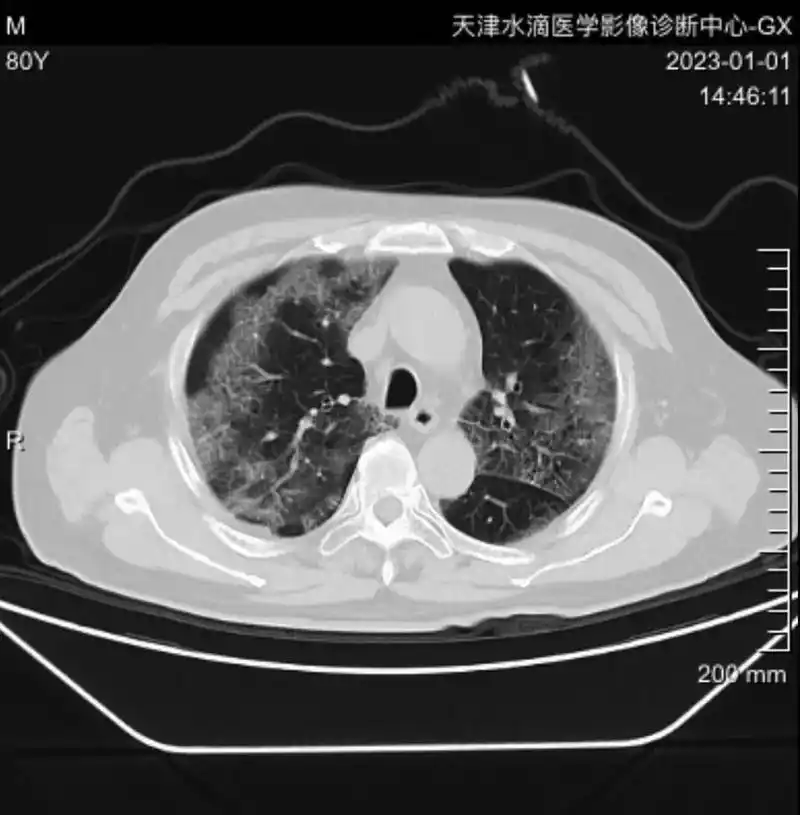

这样的ct片,算肺炎吗?求助呀

阳康后到我们单位检查胸部ct的患者.有很大一部分得了新冠肺炎 - 抖音

肺炎病例讨论

69 吸入性(化脓性)肺炎紧急求助 这个是8月4日拍的ct片

女性35岁咳喘1月胸部ct报肺炎